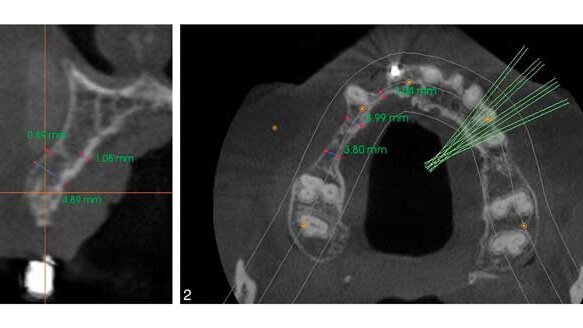

Diagnosis of alveolar bone should first be assessed visually for width and height and the relationships of teeth to one another and to the dental arch. Radiographic images can distinguish two-dimensional versus three-dimensional bone deficiency. A three-dimensional or volumetric bone evaluation with cone-beam computed tomography allows for precise measurement of the ridge and evaluation of both the cortical and medullary portion of the bone, which are imperative for the stability of the implant.